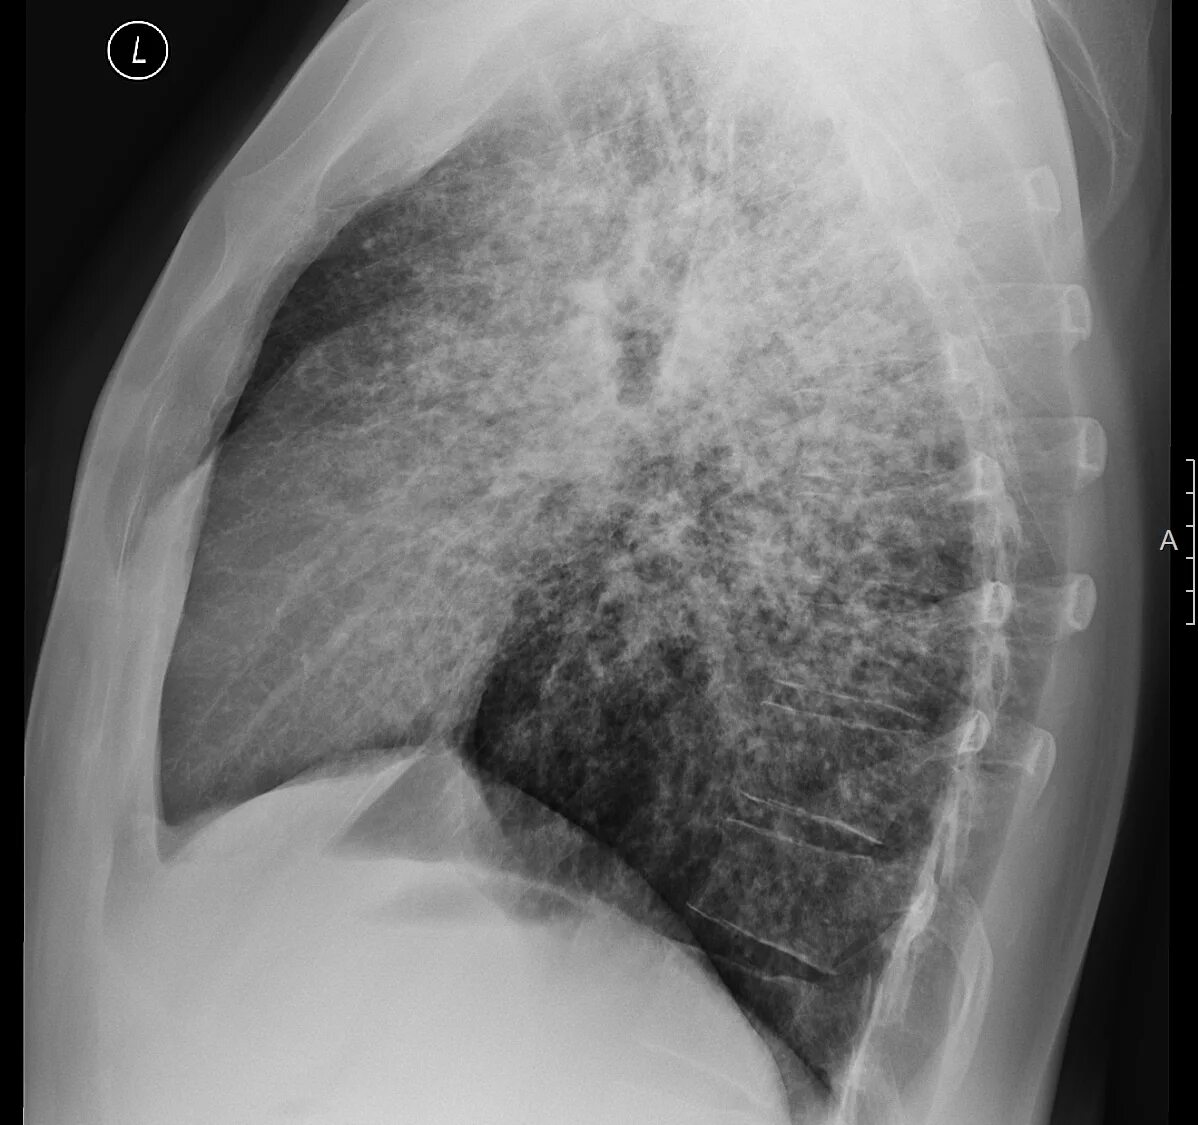

Саркоидоз 1